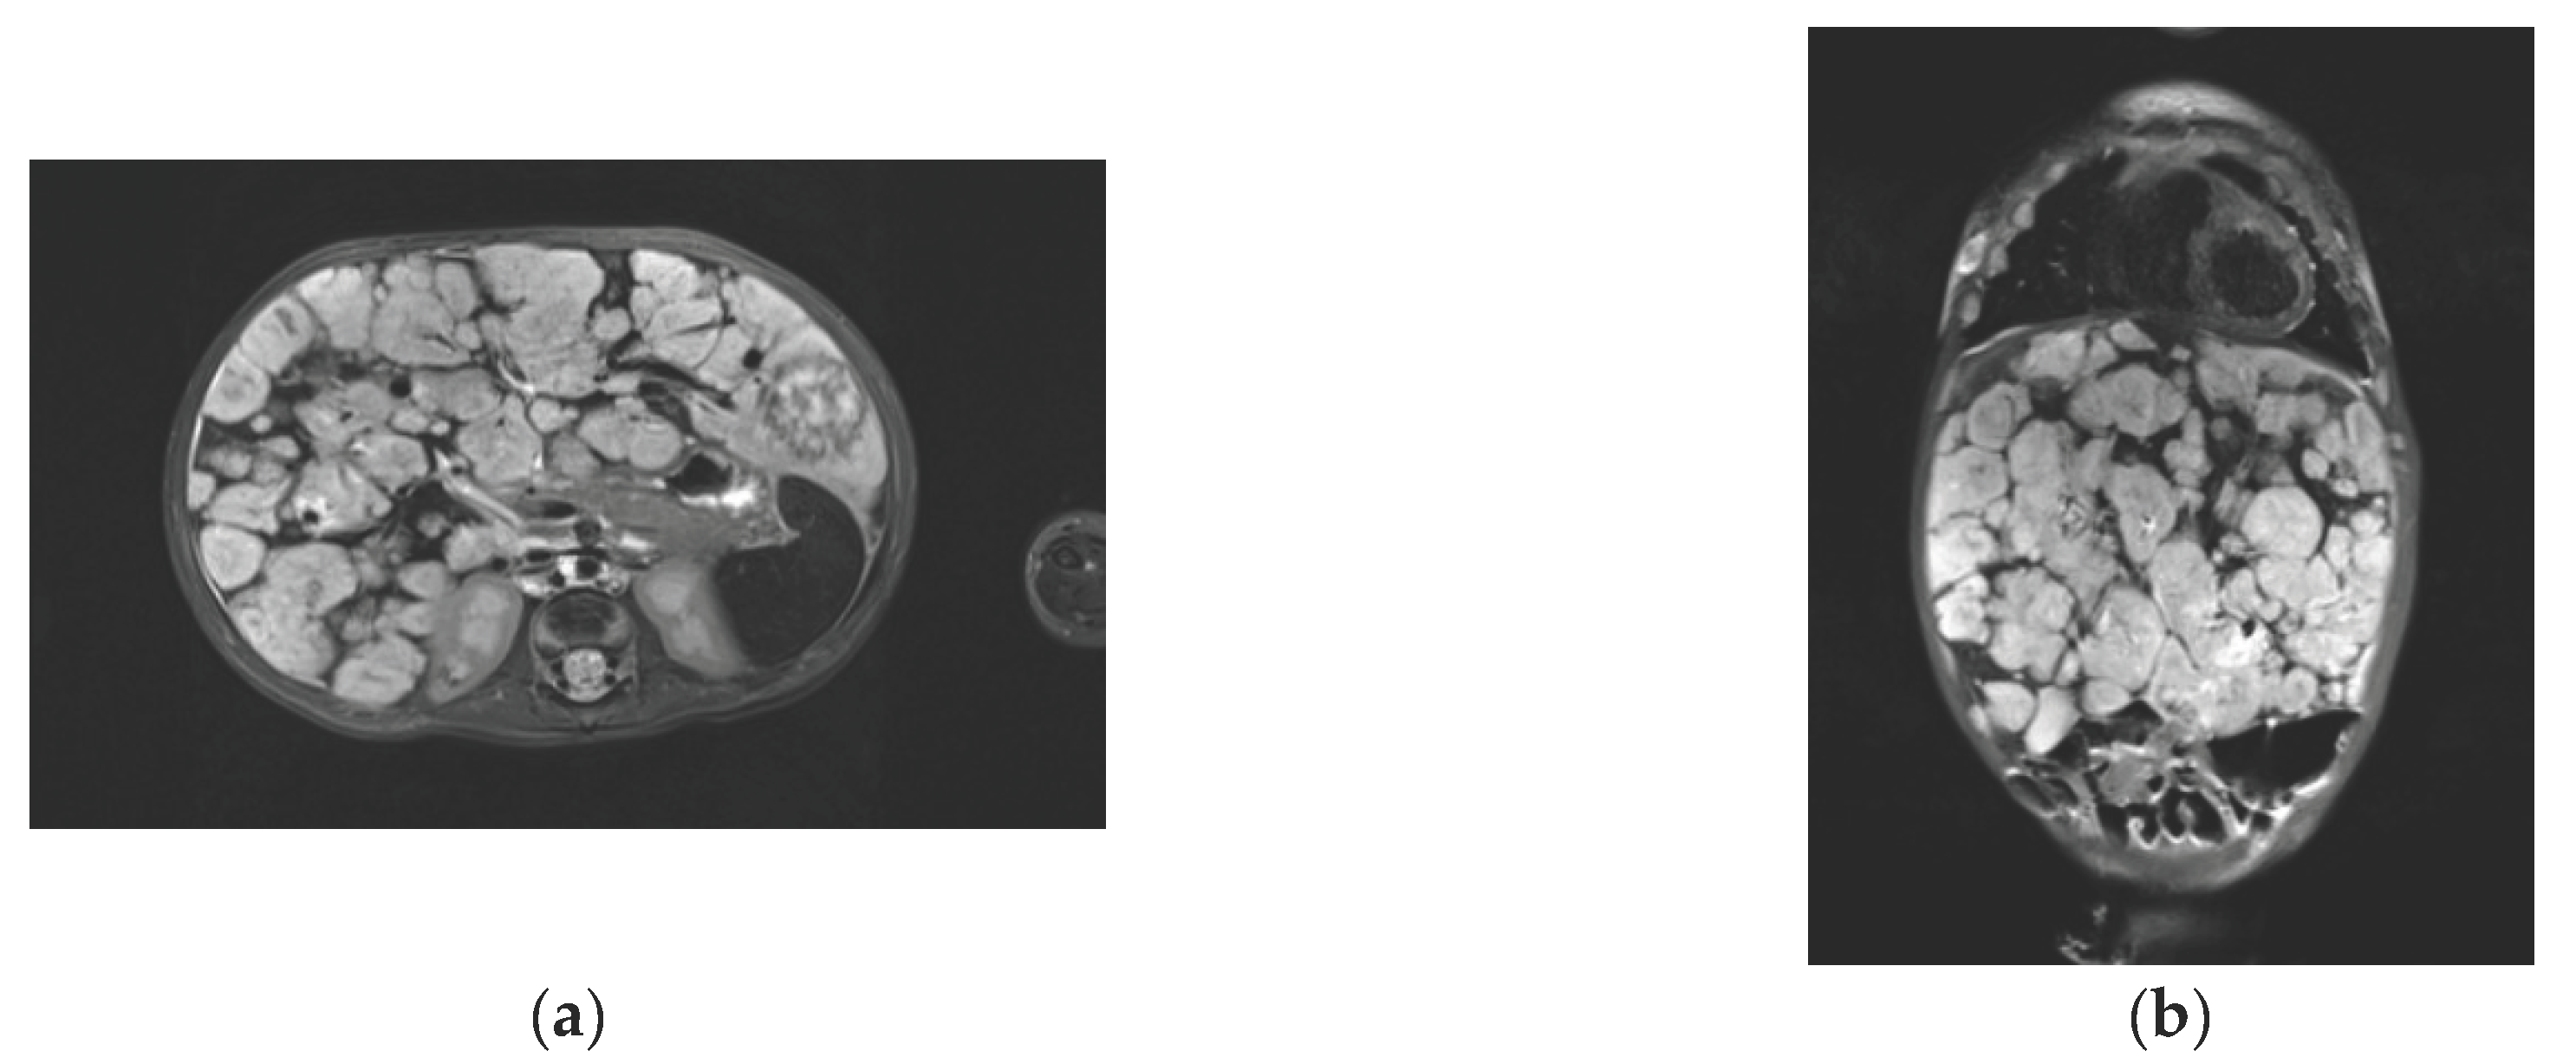

US examination of the liver — OTS (subcostal approach, oblique-transverse scanning along the edge of the costal arch at the level of the midclavicular line) reduction to 105 mm; reduction of the size of multiple focal formations to 8×12 mm; EchoCG — reduction of the size of the atrial septal defect to 5-6 mm; reduction of the heart cavities to normal size; no signs of pulmonary hypertension; MRI of the abdominal organs demonstrated a picture of liver hemangiomatosis with positive dynamics in comparison with the CT picture upon admission. The picture of the liver parenchyma had multiple irregularly shaped bulky formations up to 3.7 cm subtotally replacing the parenchyma. The centripetal type of the accumulation of the contrast by focal formations was revealed with intravenous multiphase contrasting (Figure 1a,b).

Figure 1. MRI images of the patient’s liver on day 30 of the therapy. T2-weighted images in (a) axial and (b) coronary projections present an increase in the size of both lobes of the liver due to multiple volumetric formations with clear bumpy contours. The structure of the formations is moderately heterogeneous and solid.